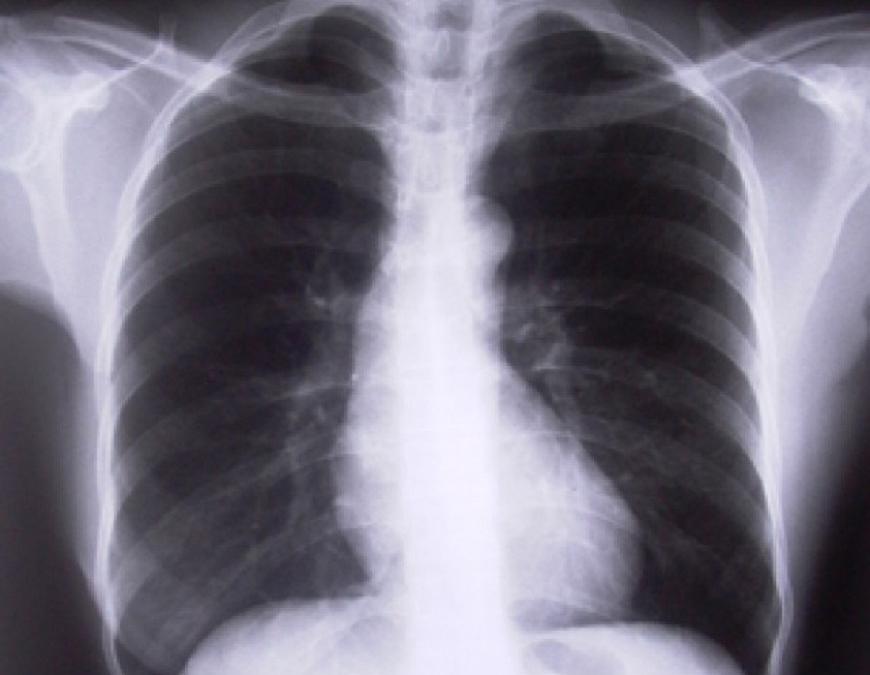

Cada 12 de noviembre se conmemora el Día Mundial contra la Neumonía, con el fin de concienciar sobre esta enfermedad mortal en niños y que constituye una amenaza para aquellas personas con factores de riesgo. La neumonía es una infección aguda de los pulmones por la...